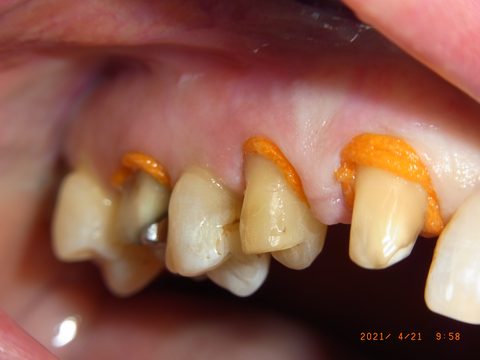

Gute Patienten- (durch Prophylaxe) und Sulcusvorbereitung (intragingivale, adrenalinhaltige Anästhesie, Faden Knit-Pak Gr. 2 (Fa. Premier) mit Racestyptine (Fa. Septodont), ca. 10 min Einwirkzeit) und möglichst knochentrockene Situation direkt vor der Abformung bleiben wichtig. (Anmerkung 7/2023: Die Abdruckspritze ist wieder dabei, weil sie die Luftblasen im Sulcus reduziert.)

Retraktionsfaden Knit-Pak Gr. 2 mit Racestyptine an den Frontzähnen des Oberkiefers: Der orange Faden öffnet den Sulcus für die anschließende Abformung.

Nahaufnahme: Der Faden liegt tief im Sulcus und verdrängt die Gingiva zuverlässig. Die knochentrockene Situation ist für eine fehlerfreie Sulcusabformung entscheidend.